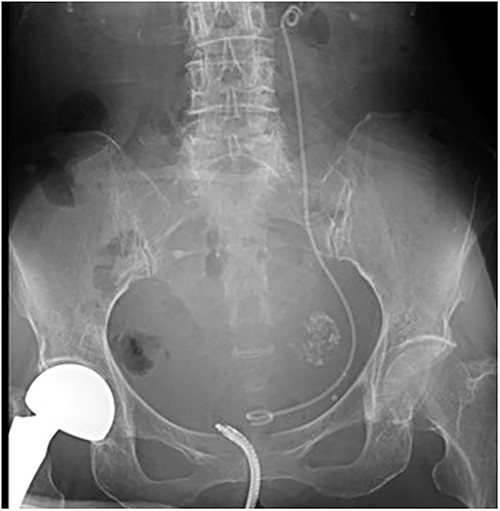

A 78-year-old woman (height, 161 cm; weight, 35 kg) had undergone total gastrectomy for gastric cancer; pathological examinations had revealed signet ring cell carcinoma with invasion into the serosa. One year and 4 months after the surgery, she presented to our hospital with fever, anorexia and weight gain. Computed tomography (CT) revealed left ureteral stricture and hydronephrosis caused by recurrent peritoneal dissemination (Fig. 1). Blood tests revealed decreased renal function and an increase in the inflammatory response. Based on these findings, a diagnosis of left obstructive acute pyelonephritis was made, prompting a decision to place a ureteral stent to relieve the obstruction. Using a flexible cystoscope fluoroscopically, a 6 Fr, 24 cm double-J ureteral stent was inserted into the left ureter. The guidewire passed smoothly, and good coiling was achieved both proximally and distally with no apparent complications (Fig. 2). Two weeks after stent placement, the patient recovered with improvements in left hydronephrosis and renal function.

A post-operative plain abdominal X-ray; the ureteral stent is properly placed as seen in a plain abdominal X-ray.

After 1 month, we replaced the migrated ureteral stent with a new 7 Fr, 26 cm double-J ureteral stent. After confirming successful postoperative urine drainage through the stent, the nephrostomy tube was removed the day after the procedure. Thereafter, the patient experienced no relapse of the left hydronephrosis or obstructive acute pyelonephritis.